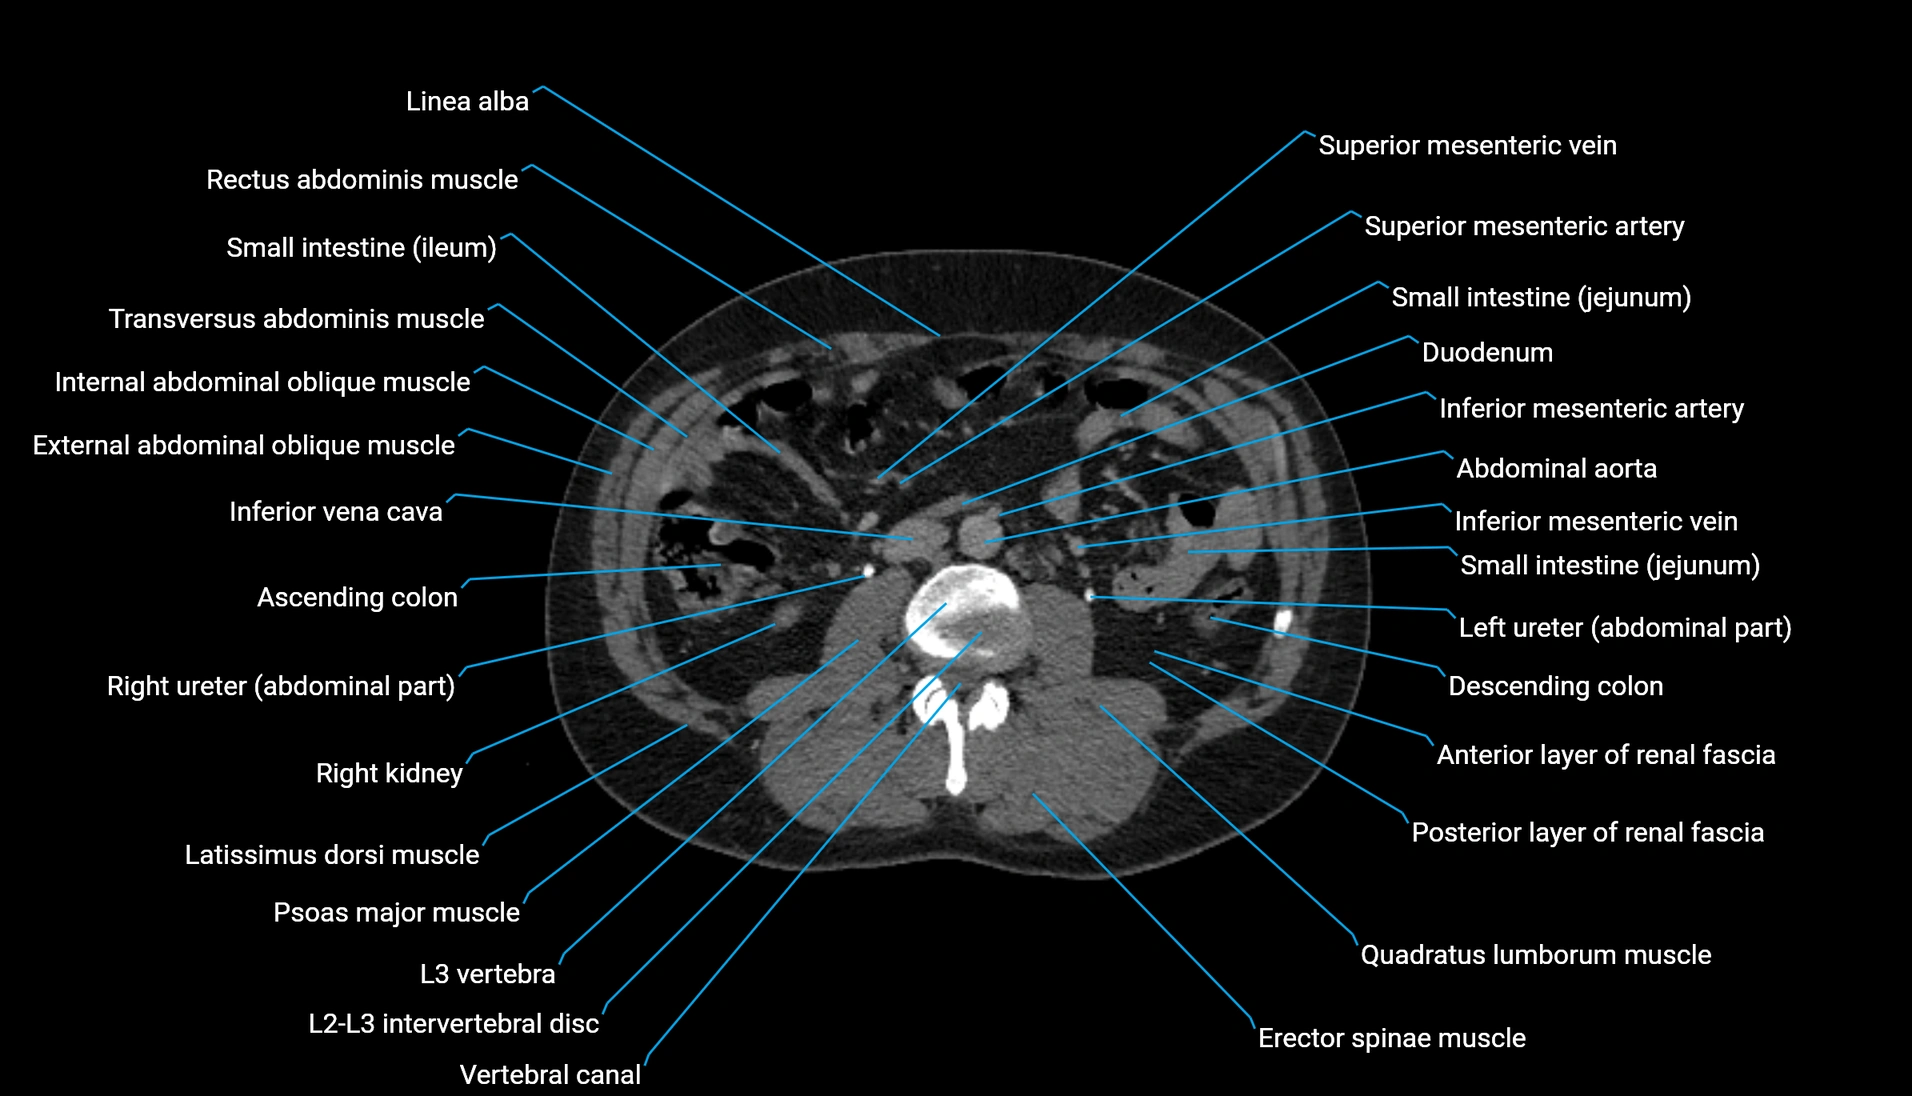

CT Appearance

Non-contrast CT:

-

Demonstrates cortical bone of acetabular rim in excellent detail

Detects fractures, dysplasia, retroversion, or bony overcoverage (pincer impingement)

3D reconstructions used in preoperative hip surgery planning

CT VRT 3D image

CT image